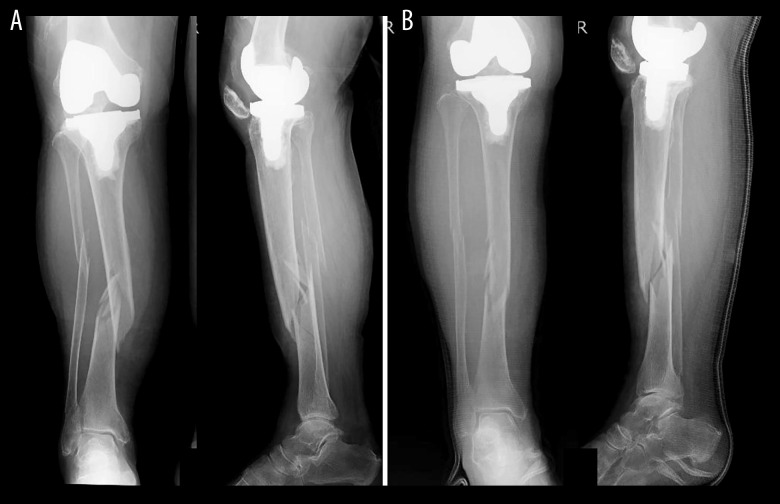

BACKGROUND Periprosthetic tibial fractures following total knee arthroplasty (TKA) are increasingly encountered in very elderly patients, where multiple comorbidities and osteoporosis compromise early mobilization and elevate the risk of complications. Maintaining pre-injury activities of daily living (ADL) while ensuring safe surgical management is challenging. We present a case of a 95-year-old woman with a periprosthetic tibial shaft fracture managed with open reduction, additional plate fixation, and Ilizarov external fixation, enabling immediate postoperative weight-bearing. CASE REPORT A 95-year-old woman who sustained a periprosthetic tibial shaft fracture after a fall had been independently ambulatory indoors and used a cane outdoors. On admission, radiographs showed a Felix Type III tibial fracture. Six days after the injury, the fracture was stabilized using Ilizarov external fixator with additional internal fixation using a small locking plate. This combined approach allowed immediate full weight-bearing from the day after surgery. She had no major complications; a minor pin-site infection was managed conservatively. Bone union was confirmed on computed tomography (CT) at 4 months, and the external fixator was removed. At 1 year, radiographs showed good alignment, and she walked independently without a cane. CONCLUSIONS This case demonstrates that combining Ilizarov external fixation with internal plate fixation can enable immediate postoperative weight-bearing and functional recovery, even in very elderly patients with periprosthetic tibial shaft fractures and severe osteoporosis.

背景:全膝关节置换术(TKA)后胫骨假体周围骨折越来越多地出现在高龄患者中,其中多种合并症和骨质疏松症损害了早期活动并增加了并发症的风险。维持损伤前的日常生活活动(ADL),同时确保安全的手术管理是具有挑战性的。我们报告了一例95岁的女性假体周围胫骨干骨折,采用切开复位、附加钢板固定和Ilizarov外固定,使术后立即负重。病例报告:一名95岁的女性在跌倒后发生假体周围胫骨轴骨折,在室内可以独立活动,在室外使用拐杖。入院时,x线片显示Felix III型胫骨骨折。受伤6天后,使用Ilizarov外固定架稳定骨折,并使用小锁定钢板进行额外内固定。这种联合方法可以在手术后的第二天立即完全负重。她没有重大并发症;轻微的针部感染保守处理。4个月时,计算机断层扫描(CT)证实骨愈合,并拆除外固定架。1岁时,x光片显示对齐良好,无需拐杖即可独立行走。结论:本病例表明,Ilizarov外固定联合钢板内固定可以使术后立即负重和功能恢复,即使是非常高龄的胫骨干周围骨折和严重骨质疏松症患者。